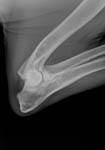

Gesundheitsstatus vom 26.11.2018 Die Röntgenbilder zeigen keinen Hinweis auf HD oder ED bei Lena vom Gehrensee. Die veterinärmedizinischen Untersuchungen von Jana auf HD, ED u. DCM und die Zuchtzulassungsprüfung wurden erfolgreich bestanden.

Die Gelenke sind HD und ED - frei, das Herz ohne Befund. Vor dem Hintergrund, dass seit 5 Generationen alle Zuchthündinnen bis ins hohe